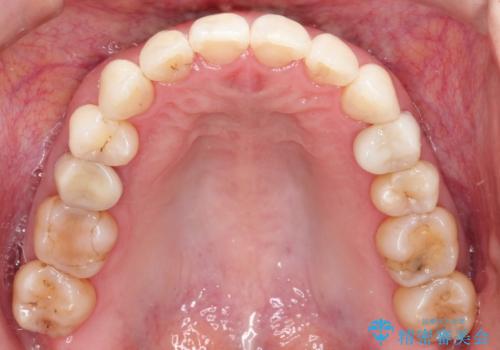

【インビザライン 】前歯を下げたい

- 前歯の凸凹と、前突を主訴に来院されました。

インビザライン にて治療を行なっております。

治療期間中はゴムかけを行なってもらうことで、前歯を下げることができました。